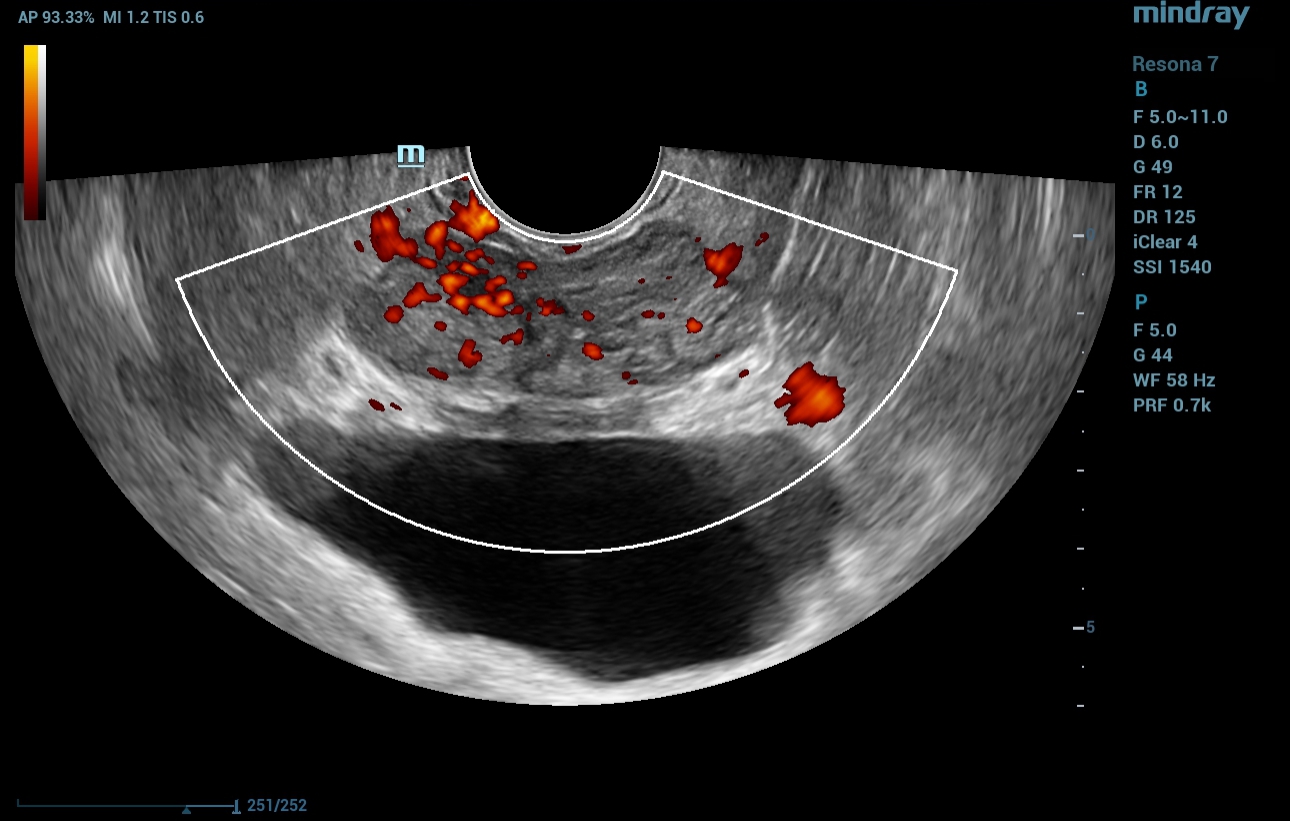

????? Resona 7 ??? ??? ??? ??? ??? ??(TRUS)? ??????. ???? ??? 36ml? ??????, ??? ??(interlobular furrow) ?? ??(right lobe) ????? ?? ?? 15mm? ????? ???? ??? ??? ??? ???????(Fig. 1).

?? ??? ??, B-?? TRUS ???? ??? ?? ??? ????? ??(vascularity) ??? ???????(?? 2).